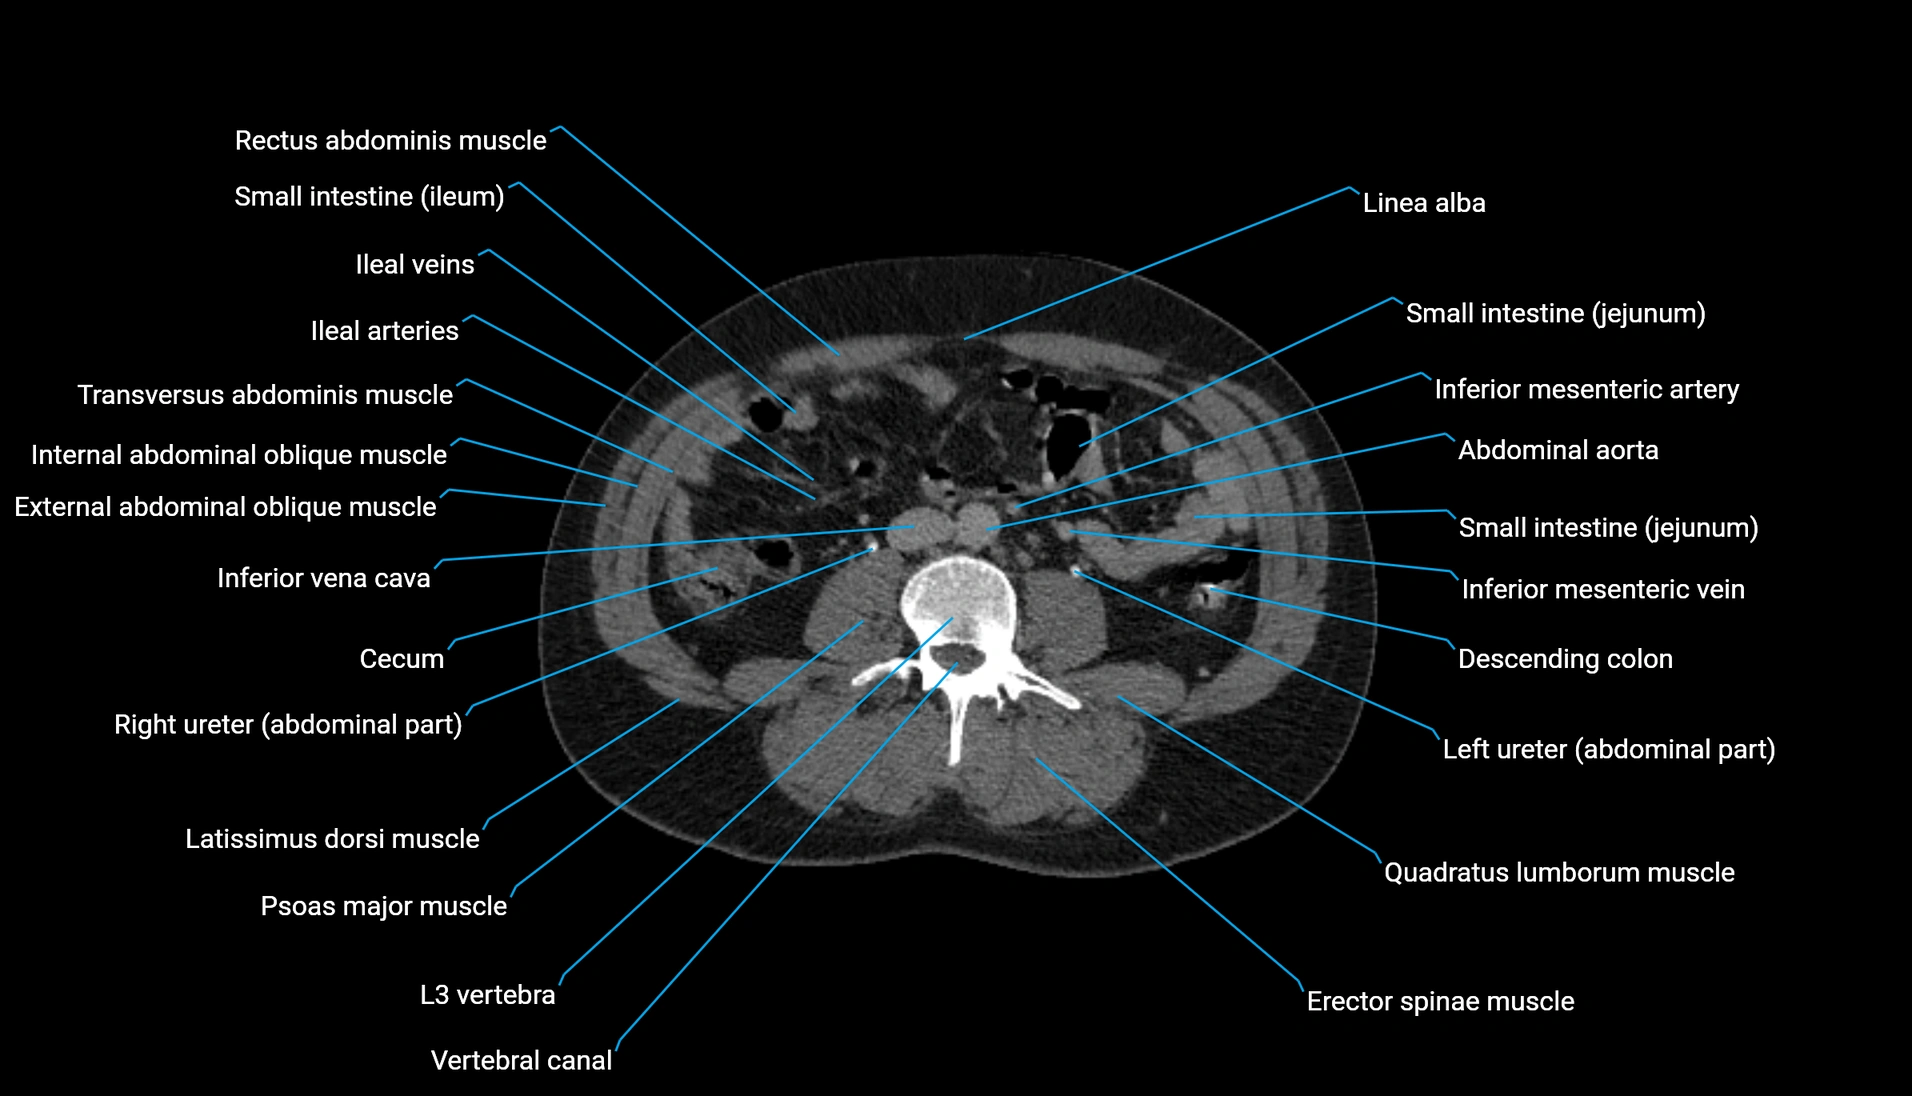

CT Appearance

Non-contrast CT:

-

Demonstrates cortical bone of acetabular rim in excellent detail

Detects fractures, dysplasia, retroversion, or bony overcoverage (pincer impingement)

3D reconstructions used in preoperative hip surgery planning

CT image